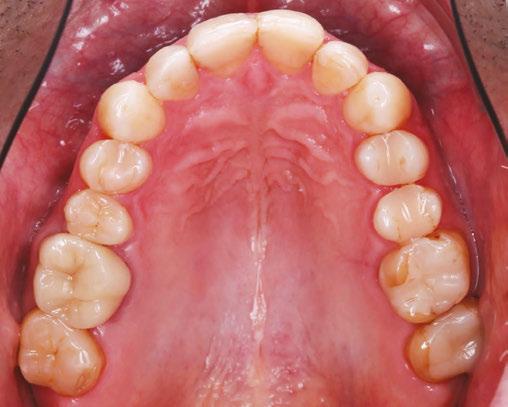

In my practice at Teeters Orthodontics in Peoria, Arizona, I have fully integrated Angel Aligner into my treatment protocols. One of the key innovations I utilize is the angelButton™, a unique feature designed to enhance sagittal bite correction and correct crossbites more efficiently and effectively. By incorporating these built-in buttons with elastics, I am able to achieve more predictable and efficient outcomes for my patients, improving their overall bite alignment with greater precision.

Additionally, I have embraced the A6 Mandibular Advancement solution to help patients with mandibular retrusion. This system allows me to simultaneously correct occlusion issues while advancing the mandible, leading to improved facial profiles and functional benefits. Having utilized the twin block in practice for over 12 years with remarkable results, I have embraced this new technology to combine orthopedic and orthodontic treatment in a single phase, reducing overall treatment time while delivering superior results.